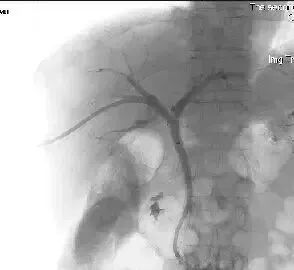

(1)经皮肝穿胆道引流(Percutaneous transhepatic choledochus drainage,PTCD或PTD)由于恶性(如胆管癌、胰头癌)或良性(如总胆管结石)病变,引起肝外胆道梗阻,临床出现黄疸。PTCD可行胆道内或胆道外胆汁引流,故而缓解梗阻,减轻黄疸,为根治手术提供有利条件。行PTCD前需先做经皮肝穿胆管造影(Percutaneous transhepatic),确定胆管梗阻的部位、程度、范围与性质。PTCD有内外引流之分,通过PTC的穿刺针引入引导钢丝,而后拔出穿刺外地,沿引导钢丝送进末段有多个侧孔的导管,导管在梗阻段上方的胆管内,其内口亦在该处,胆汁经导管外口连续引流,是为外引流;若导管通过梗阻区,留置于梗阻远端的胆管内或进入十二指肠,胆汁则沿导管侧孔流入梗阻下方的胆管或十二指肠,是为内引流。

(4)应用穿刺术+PTA+Stent治疗门脉高压症,布加氏综合症。